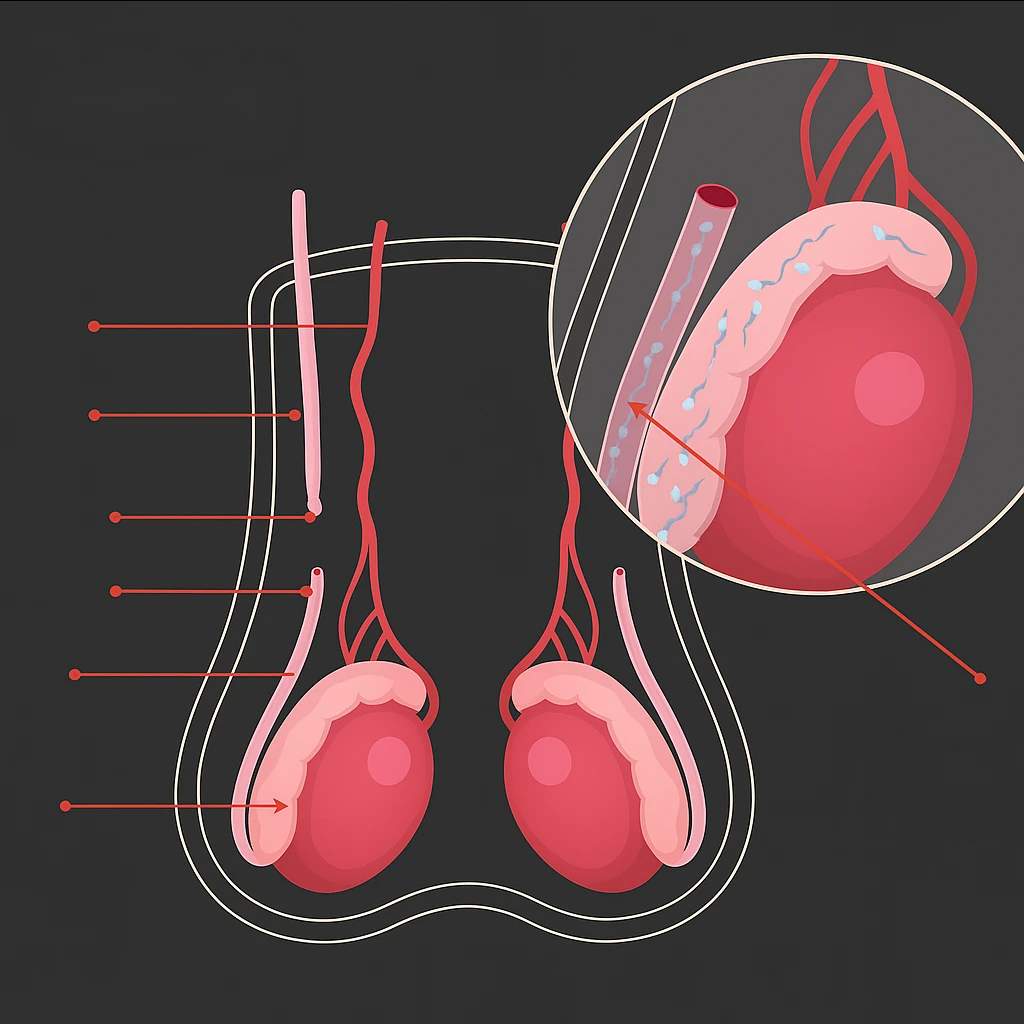

Procedimento seguro, rápido e com alta taxa de eficácia. Ideal para homens que desejam uma contracepção definitiva, com recuperação rápida e acompanhamento completo.

Procedimento seguro e definitivo para homens que desejam contracepção com rapidez, eficácia e recuperação tranquila.

Procedimento seguro, rápido e com alta taxa de eficácia. Ideal para homens que desejam uma contracepção definitiva, com recuperação rápida e acompanhamento completo.